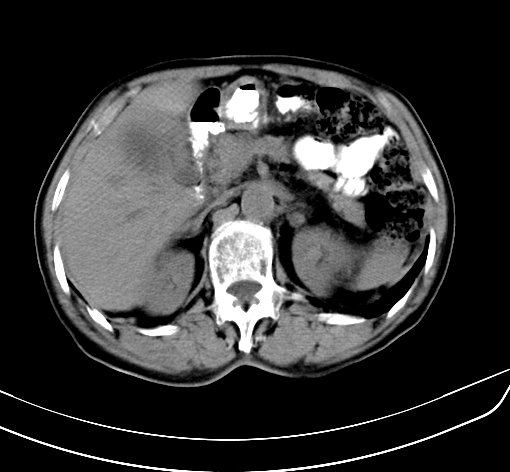

病人 男 70 咳嗽 胃部不适 2月余

胆囊壁增厚,与临近肝实质边界不清,临近肝实质内可见大片边界不清之低密度区,肝门区密度亦有减低,部分结构不清,尾叶前方可见块状影,肝右叶可见多枚边界不清之圆形低密度区,肝内胆管扩张征象,结合病史考虑1胆囊癌肝内转移,肝门区淋巴结转移,门脉癌栓待排2肝内胆管扩张3建议增强扫描

肝脏多发大小不等低密度灶,边界不清,肝门区结构不清,肝内胆管轻度扩张,胆囊密度不均匀,内见软组织样密度影,与相临肝脏边界不清.考虑:1、胆囊ca侵犯肝脏并肝内多发转移,肺上也有结节影,转移?建议强化扫描.2、胃充盈不好,如怀疑有病变最好建议做相关检查.

胆囊壁增厚,周围模糊不清,肝内多发低密度影,胃充盈欠佳,胃壁增厚,外形尚规整,考虑胆囊炎、胆囊癌肝内转移?建议胃肠道进一步检查或增强扫描。